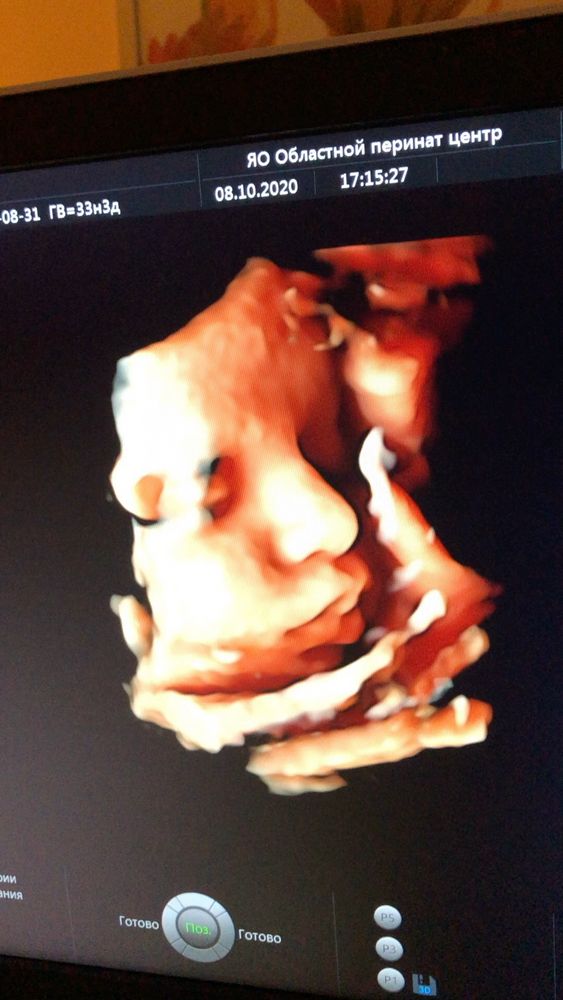

вот в 34 ещё делали)) Обычно все детки поджимают нижнюю губу,наш наоборот,выпячивает 😀ой,я так рада была,когда увидела его губы))) у мужа пухлые,красивые,как раз хотела,чтобы как у мужа были))

20.10.2020